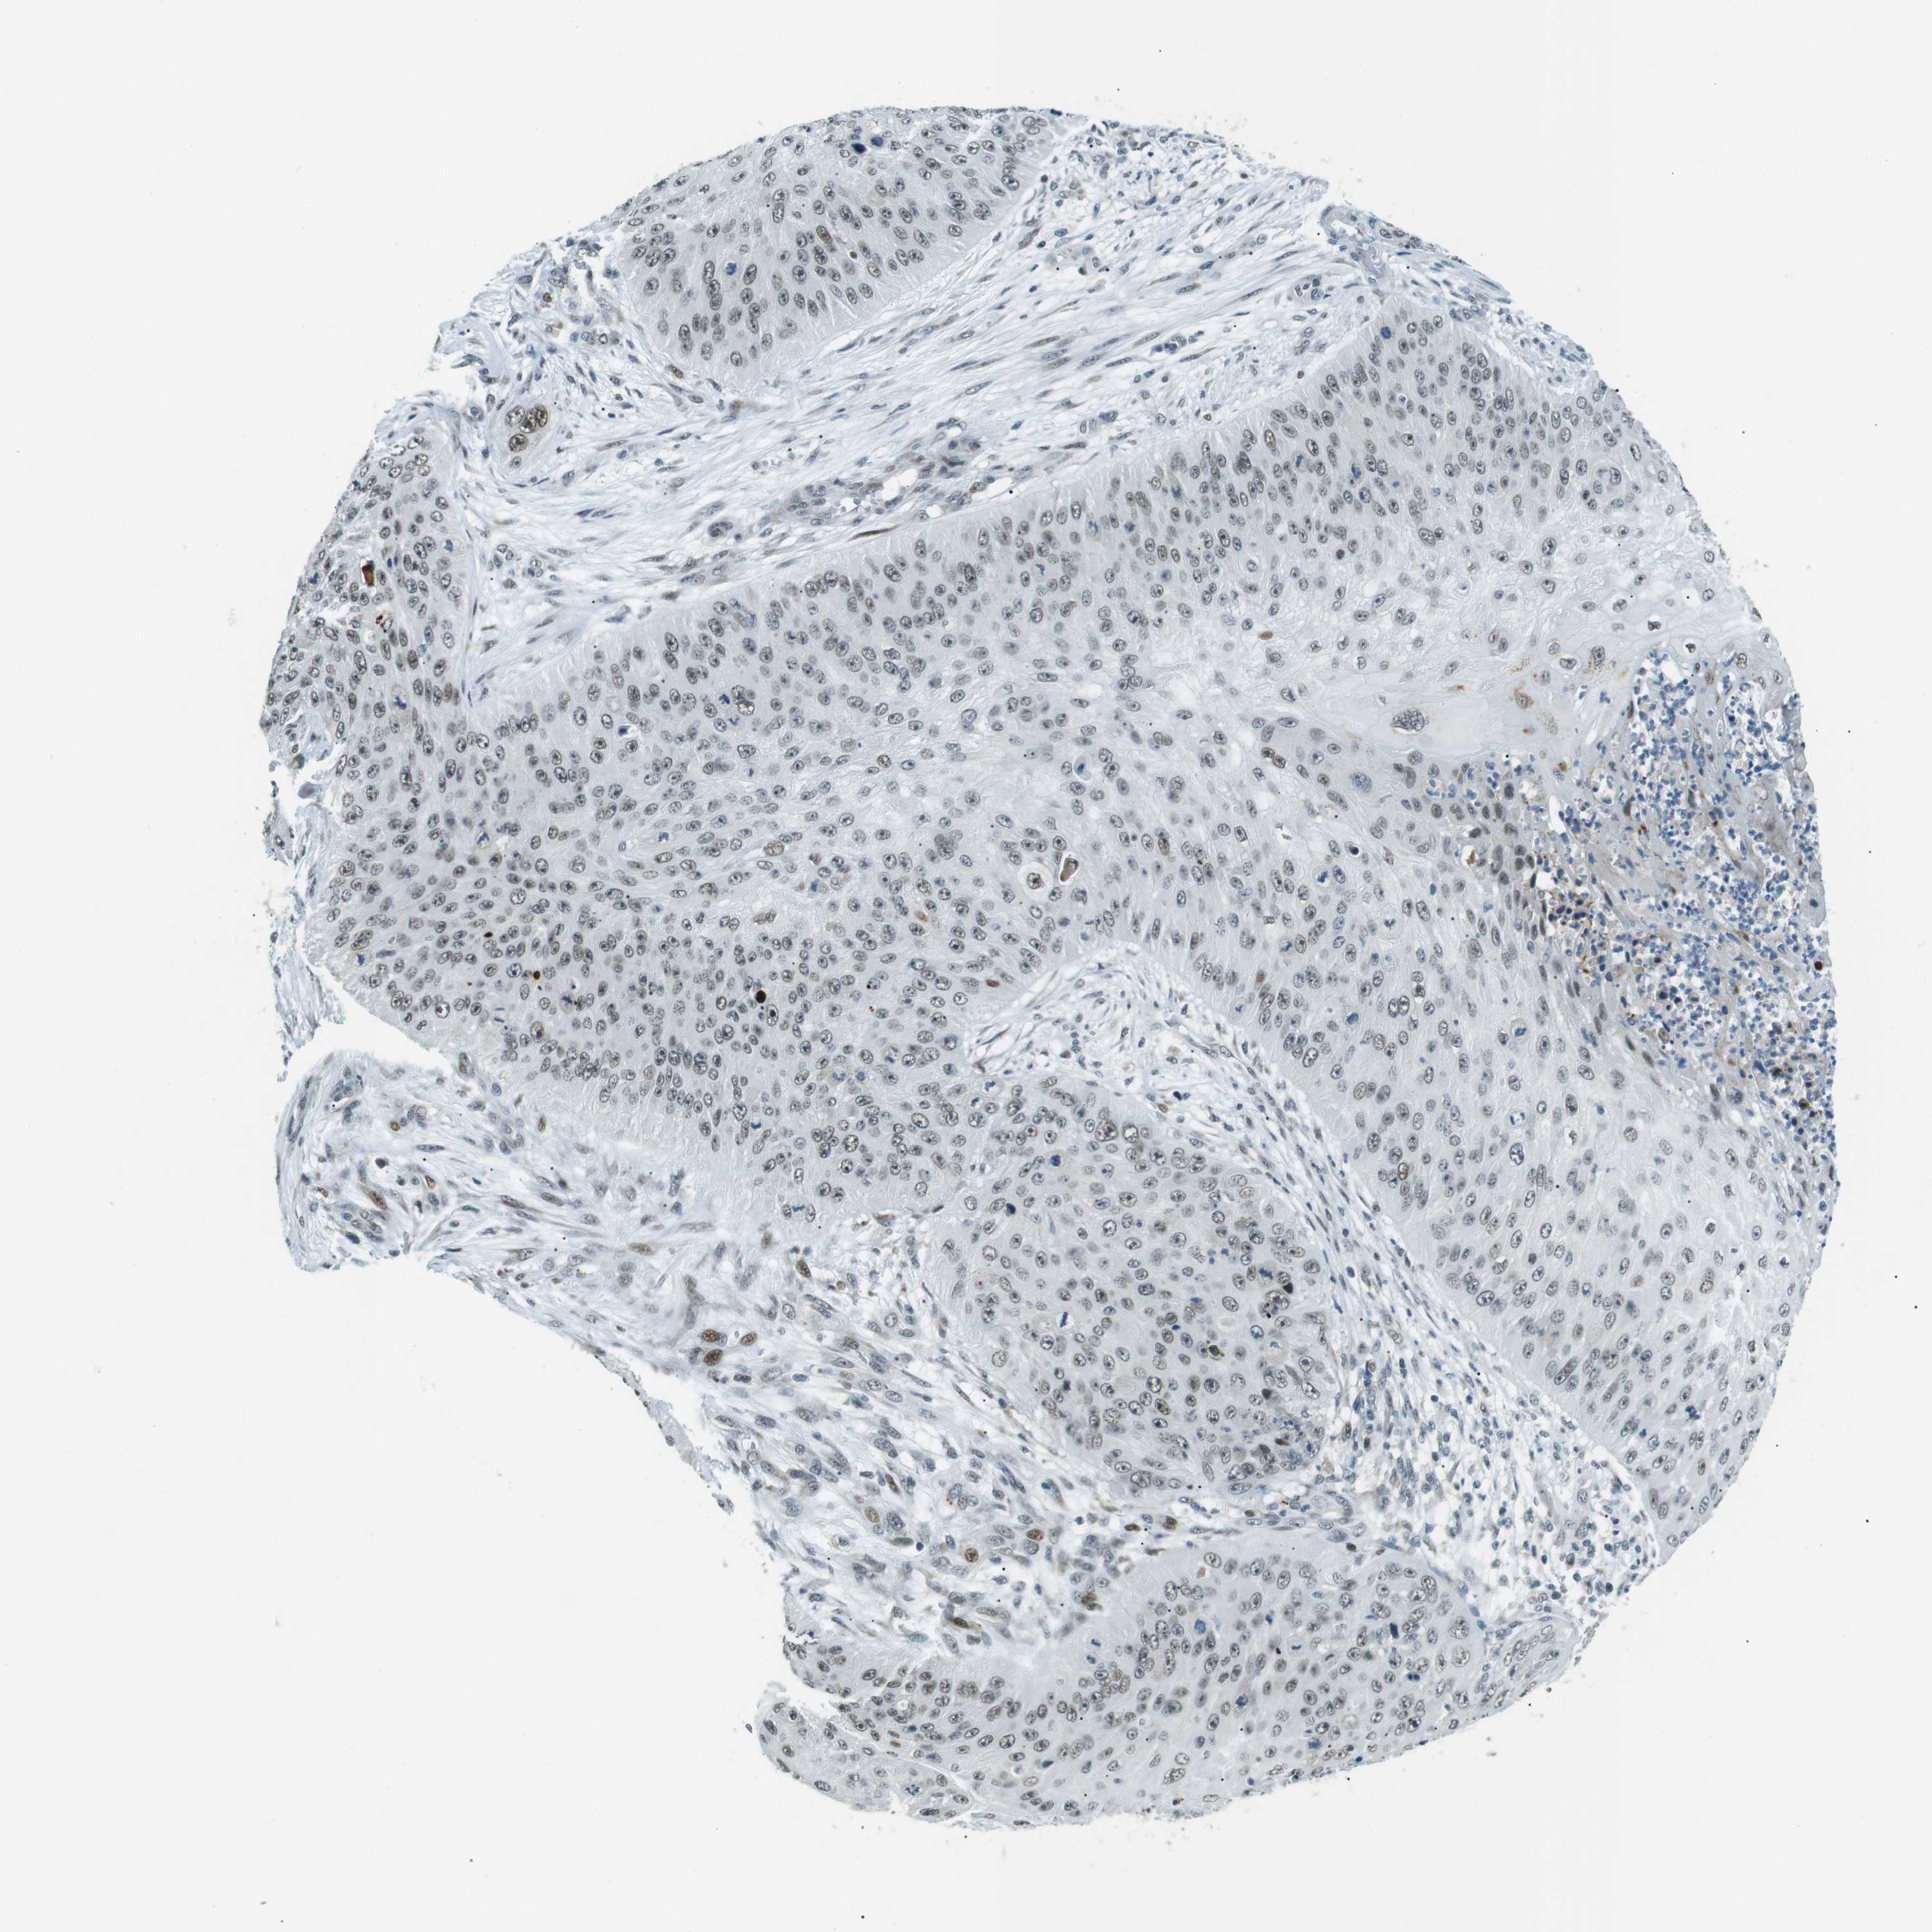

CANCER SKIN CANCER Show tissue menu

SKIN CANCER - Protein expressioni

A mouse-over function shows sample information and annotation data. Click on an image to view it in a full screen mode. Samples can be filtered based on level of antibody staining by selecting one or several of the following categories: high, medium, low and not detected. The assay and annotation is described here.

Each image is clickable and will lead to virtual microscopy that enables deeper exploration of all samples and also displays staining intensity scores, fraction scores and subcellular localization as well as patient and tissue information for each sample.

Antibody HPA000595

Staining

High

Medium

Low

Not detected

Intensity

Strong

Moderate

Weak

Negative

Quantity

>75%

75%-25%

<25%

None

Location

Nuclear

Cytoplasmic/membranous

Cytoplasmic/membranous,nuclear

Squamous cell carcinoma in situ, NOS

Squamous cell carcinoma, NOS

Basal cell carcinoma

Adnexal tumor, benign